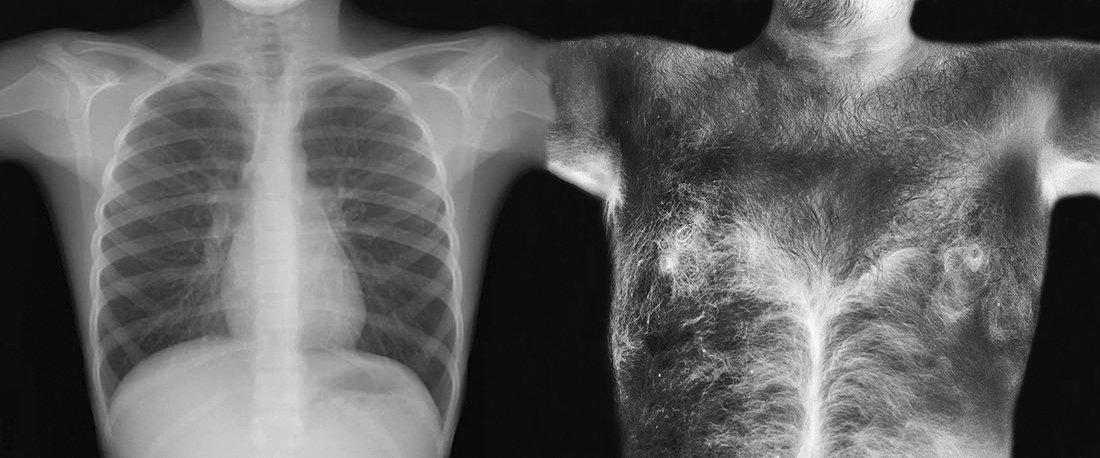

With a look devoid of fears, almost analytical, the author studies, through his own body, his three states or realities: the external (epidermis), the internal, and the inevitable future that is to come (it is said that we started to die from the moment we are born) .